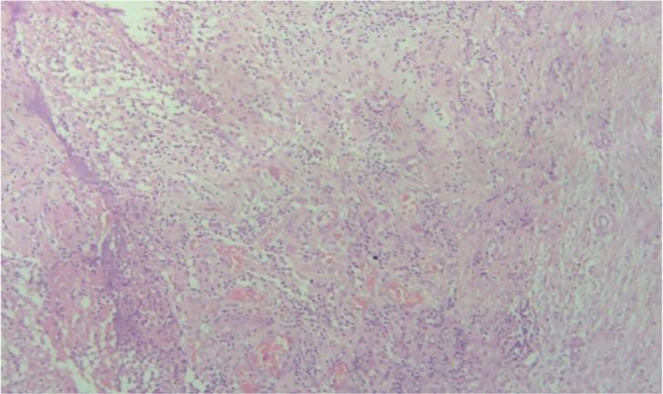

Case report: We report a case of a 26-year-old female presenting with painful swelling at a caesarean section scar, previously excised for similar complaints. Physical examination revealed a solid soft tissue mass on the scar. Magnetic resonance imaging (MRI) identified a 2x2 cm lesion in the right abdominal wall, suggestive of suture granuloma. Surgical excision revealed prolene suture material within the granulomatous tissue. Histopathology confirmed foreign body reaction.

Conclusion: Recurrence post-prior excision underscores the importance of complete granuloma removal. Differential diagnoses included scar endometriosis and inflammatory lesions. Suture granulomas, though rare, require consideration in scar-related swelling. Collaboration between specialties ensures accurate diagnosis and management.